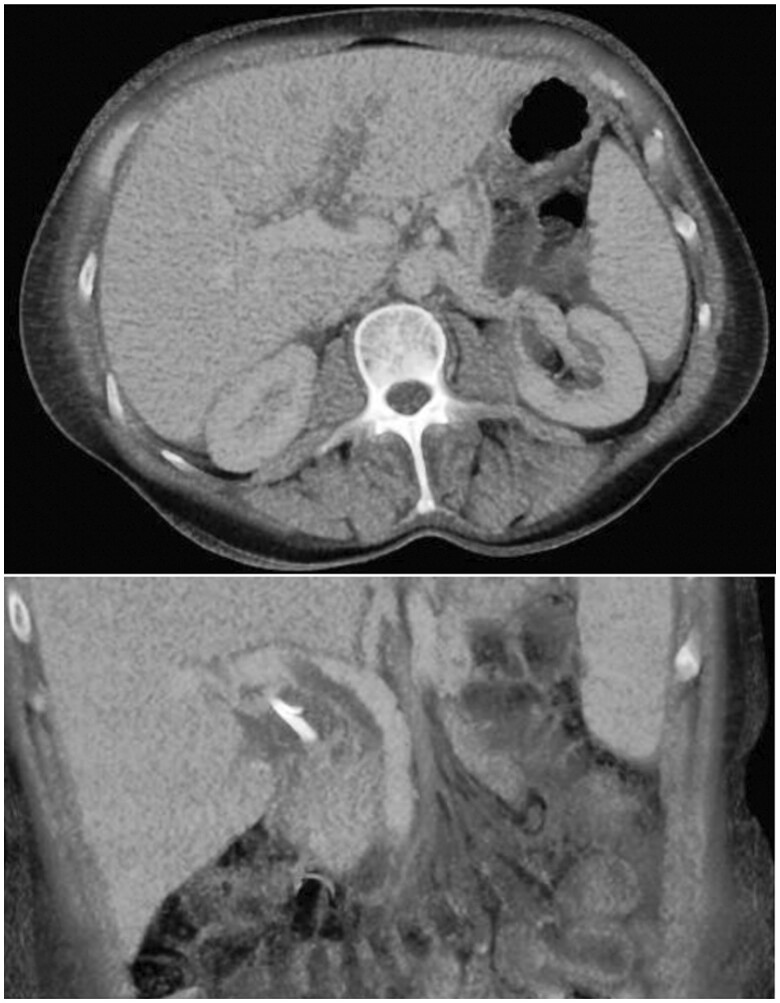

严重胰腺炎后逆行胆管造影(ERCP)是罕见的发生。更罕见的是,在ercp诱导的胰腺炎后可能出现的其他非胰腺症状,如胰腺炎和多发性关节炎。这种症状的组合被认为是胰腺炎、胰膜炎和多关节炎综合征(PPPS)。PPPS典型表现为红色皮下结节,主要发生在下肢。在某些情况下,病情可能进展到骨骼,引起髓内脂肪坏死/骨梗死。关节并发症包括多关节炎,影响大小关节。PPPS往往发生在临床胰腺炎高峰后3-6周。在本报告中,我们提出了一例PPPS作为ERCP后并发症发生的病例。由于菌血症和真菌血症的存在,这一特殊病例进一步复杂化,导致随后发展为多灶性骨髓炎。本报告中包含的医学影像提供了整个临床过程的全面概述,从最初的术后并发症和胰腺炎开始,随后使用超声和MRI进行多模态成像,描绘了睫状体炎,最后说明了多灶性骨髓炎的发展。本病例为探讨和了解胰腺炎相关的两种罕见并发症:PPPS和多灶性骨髓炎提供了机会。

Severe pancreatitis following retrograde cholangiopancreatography (ERCP) is an infrequent occurrence. Even rarer are the additional non-pancreatic symptoms that can emerge after ERCP-induced pancreatitis, such as panniculitis and polyarthritis. This combination of symptoms is recognized as the pancreatitis, panniculitis, and polyarthritis syndrome (PPPS). PPPS typically manifests as reddish subcutaneous nodules, primarily in the lower extremities. In some cases, the condition may progress into the bones, causing intramedullary fat necrosis/bone infarcts. Joint complications involve polyarthritis and affect both small and large joints. PPPS tends to develop 3-6 weeks after the peak of clinical pancreatitis. In this report, we present a case of PPPS that occurred as a complication following ERCP. This particular case became further complicated by the presence of bacteraemia and fungaemia, leading to the subsequent development of multi-focal osteomyelitis. The medical imaging included in this report provides a comprehensive overview of the entire clinical course, starting from the initial post-procedural complication and pancreatitis, followed by multi-modal imaging depicting panniculitis using ultrasound and MRI, and finally illustrating the development of multi-focal osteomyelitis. This case serves as an opportunity to explore and understand 2 rare complications associated with pancreatitis: PPPS and multi-focal osteomyelitis.